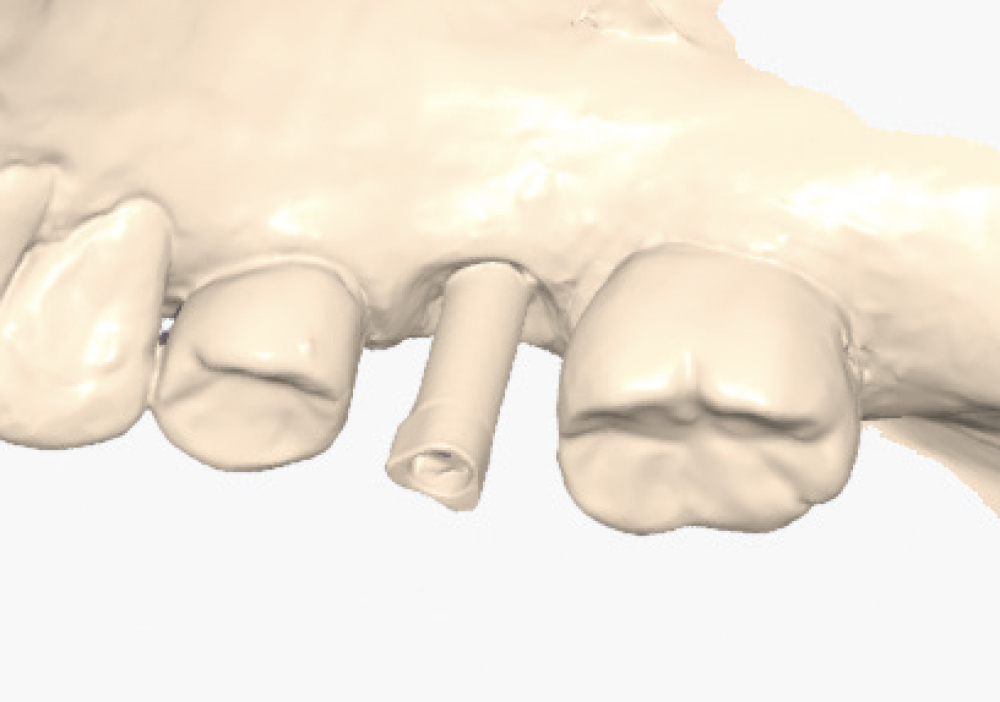

Implant post scan on left side of mouth

Implant post scan pointing down

Implant post scan close up

Verify the Scans Before Dismissing the Patient. Review all critical areas while the patient is still in the chair, ensuring complete scan body capture, accurate contacts, adequate tissue detail, and proper bite registration. Zoom in on critical areas to verify resolution and completeness. It takes only two minutes to verify a scan, but potentially days before a patient is able to return to your practice. Use the scanner’s analysis tools to identify distortions or artifacts.